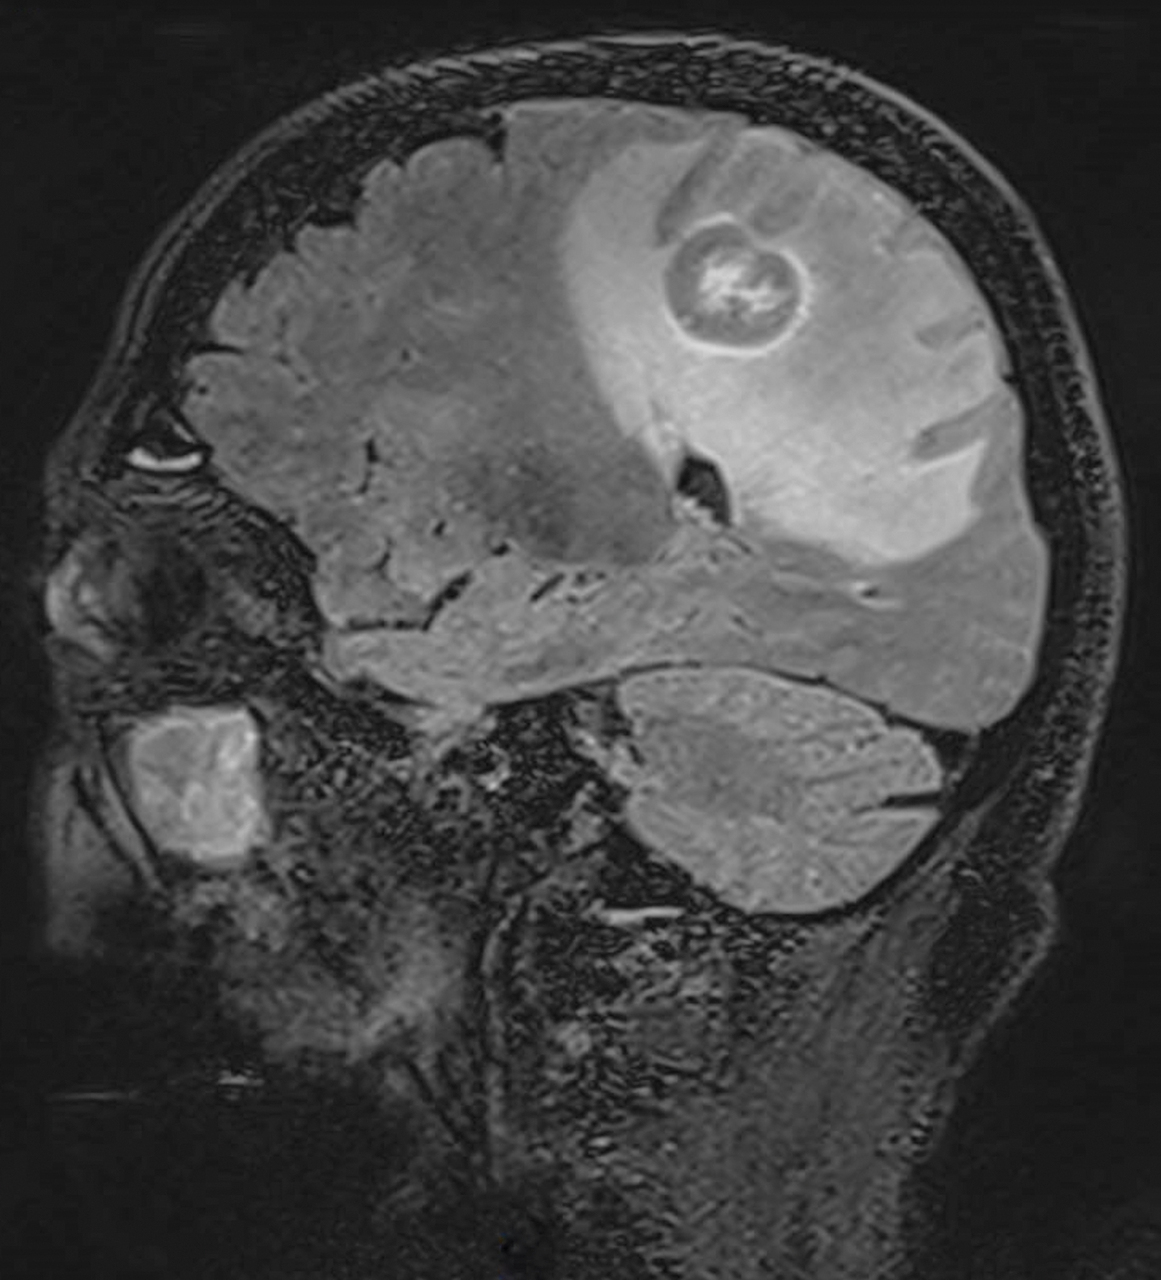

Un homme de 75 ans est hospitalisé pour une hémiparésie gauche. L’IRM cérébrale montre des lésions frontopariétales droites.

Quel est votre diagnostic ?